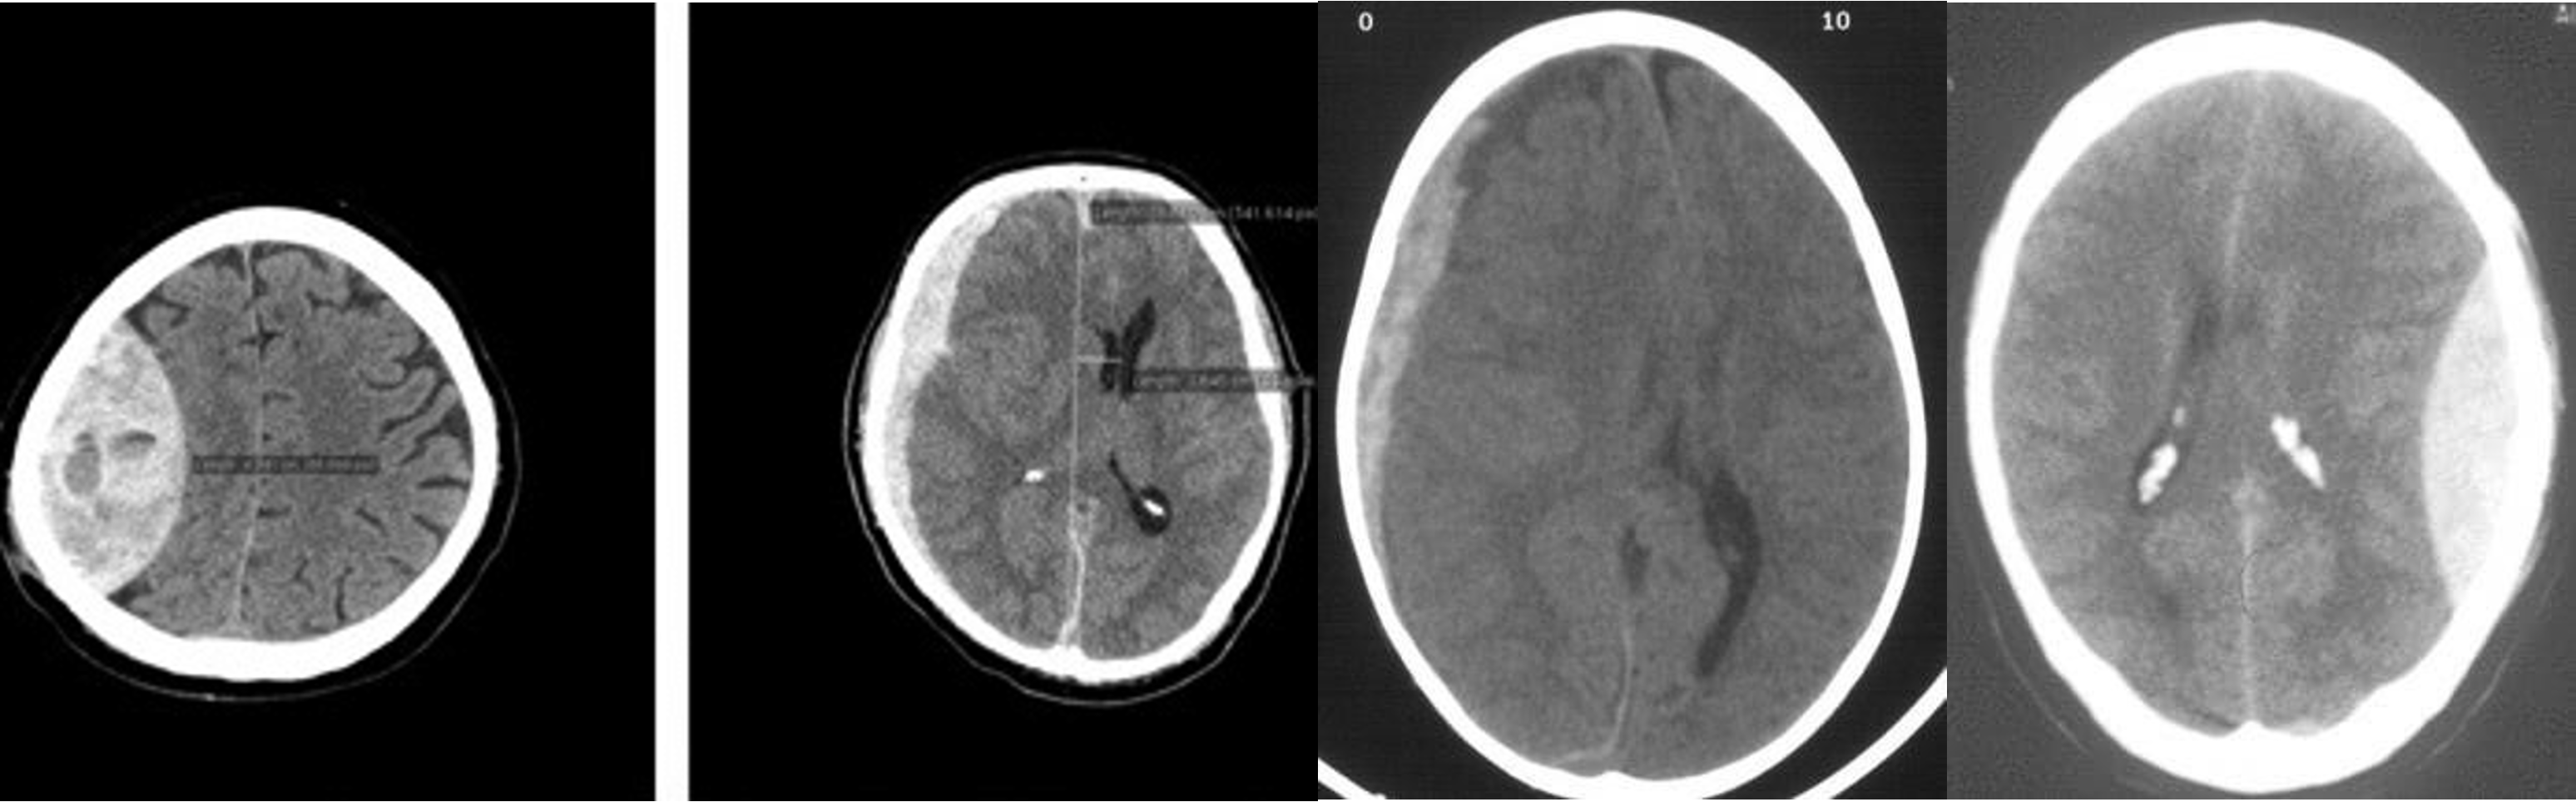

Brain Imaging

Epidural

- ipsilateral pupil diltation

Treatment: ligation of artery

Subdural

Bridging vein from brain to dural space - commonly elderly/pediatrics

s/s

- chronic

- change in personality

- hx of minor truama

Treatment Purr hole

- Epidural - shifted lenticular

- Subdural - crescent

- Subdural -

- Epidural